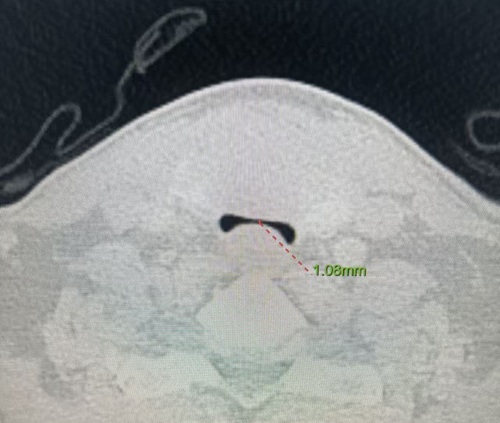

患者薛伯伯罹患甲状腺乳头状癌,肿瘤不仅侵犯被膜及周围结缔组织,更严重压迫气管,导致气管变形。CT提示气管受压显著,随时可能发生气管塌陷或术中大出血,引发窒息风险。此类病情常涉及气管切除重建、神经保护、术后气管插管及ICU监护等多重挑战。

面对这一复杂病例,乳甲外科迅速联合麻醉科、耳鼻喉科、呼吸内科、重症监护室等相关科室组成多学科诊疗团队。团队通过三维重建技术精准评估病情,于1月22日为患者施行“全麻下双侧甲状腺癌扩大根治术+淋巴结标记+双侧喉返神经探查+甲状腺自体移植术”。术中见峡部约5cm肿块与气管紧密粘连,气管壁软化、受压明显,团队使用超声刀精细分离,完整切除肿瘤。术后因患者存在气管软化风险,转入ICU密切监护,1月27日顺利拔除气管插管,转回乳甲外科继续康复治疗。

图1术中狭窄的气管;图2术前气管影像;图3术后气管影像